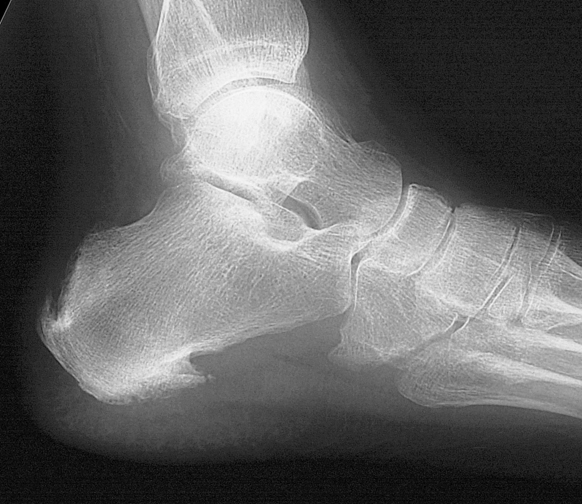

From www.jrheum.org

Heel Enthesopathy of Diffuse Idiopathic Skeletal Hyperostosis What Is Spinal Enthesopathy Lumbar Region your lumbar spine is the lower back region of your spinal column or backbone. Tendons are the tissues that attach your muscles to your bones. enthesopathy refers to pain and inflammation around your joints. This includes your wrists, knees, and ankles. spinal enthesopathy is a pathological condition involving the ligaments present in the spinal canal. ^ ball,. What Is Spinal Enthesopathy Lumbar Region.